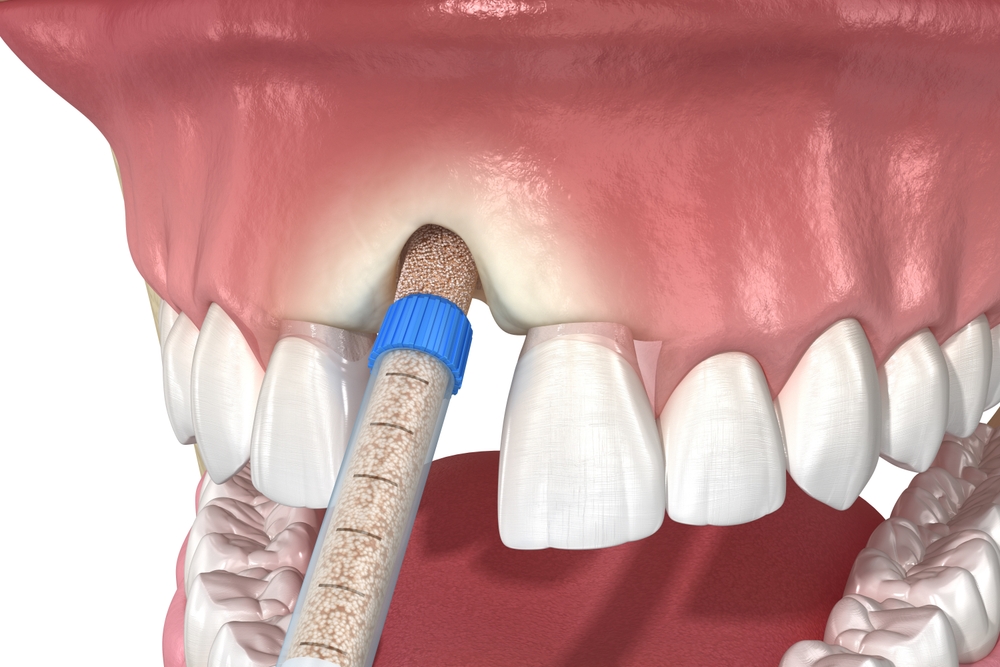

구강세정기 사용으로 청결 유지

칫솔질과 치실만으로는 임플란트

주위 깊은 부위까지 완벽히

세척하기 어렵습니다.

이럴 때 구강세정기를 함께

사용하는 것이 임플란트 관리법에서

큰 도움이 됩니다.

물의 압력을 이용해 잇몸 사이에

낀 찌꺼기를 제거할 수 있으며,

염증 가능성을 줄이는 데도 효과적입니다.

단, 너무 강한 수압은 잇몸에

자극을 줄 수 있으므로

중간 단계 정도의 세기로

사용하는 것이 좋아요.